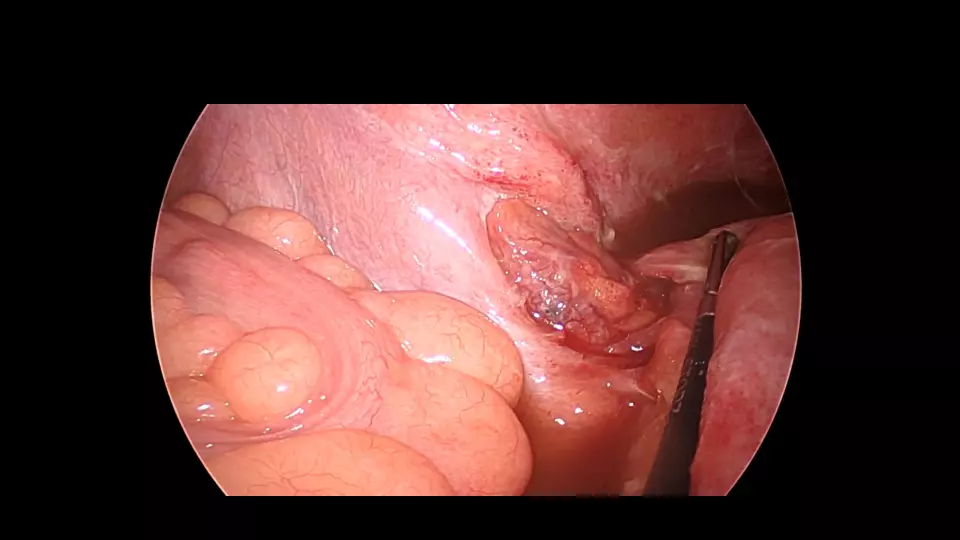

「反跳痛があります」と記載された紹介患者や、研修医からコンサルトにおいて、意外と腹膜炎ではないパターンが散見されます。 若手外科医だからこそ語れる腹膜炎のはなしを聞いてください。 #腹膜炎,#反跳痛の診かた,#コンサルト,

外科医目線の腹膜炎 ~これが腹膜刺激兆候です~